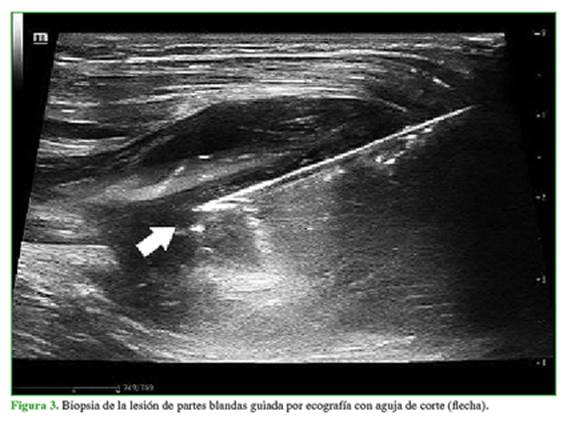

Ante la sospecha de una asociación entre lesiones óseas, interpretadas como displasia fibrosa y lesión de partes blandas, se solicita una biopsia de la masa de partes blandas (Figura 3), con confirmación histológica de mixoma intramuscular (Figura 4), que configura un síndrome de Mazabraud.